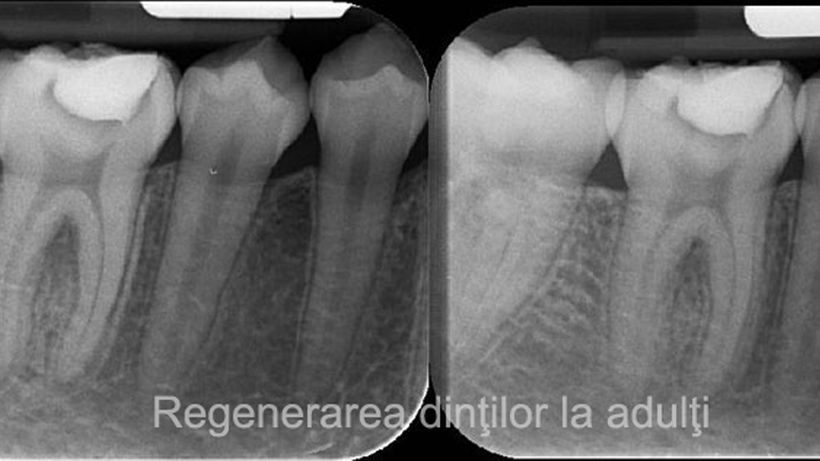

Descoperire uluitoare în medicină. Un medicamant uzual poate regenera dinții

Deși pare contraintuitiv, un medicament folosit de pacienții ce suferă de boala Alzheimer are capacitatea de a regenera dinții utilizatorilor. Dezvoltat și testat pentru a trata boala Alzheimer, medicamentul se întâmplă, de asemenea, să ajute mecanismul natural de regenerare a dinților. Tideglusib funcționează prin stimularea celulelor stem din pulpa dinților, sursa de dentină nouă. Dentina […]